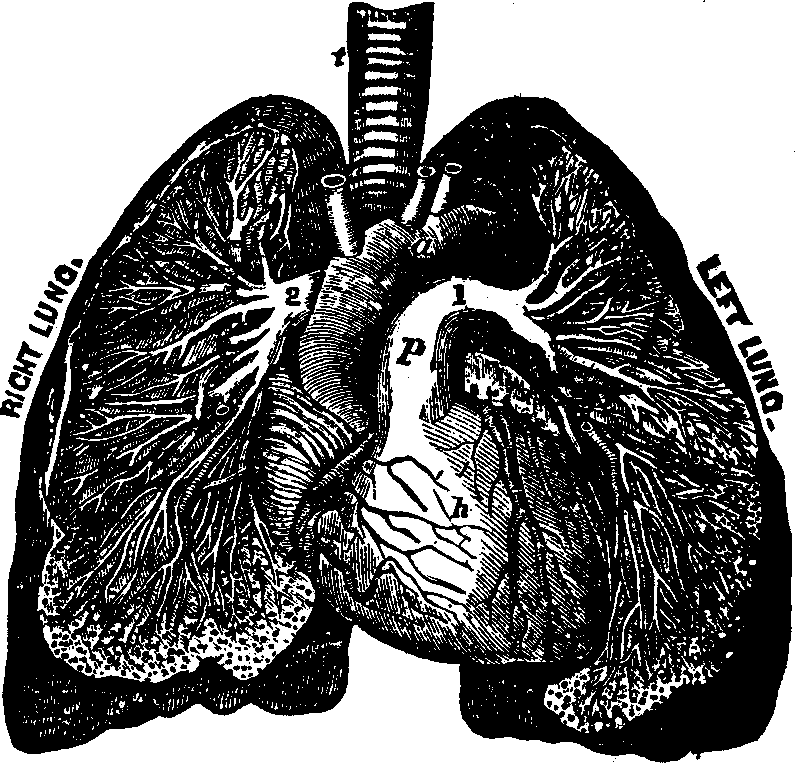

The Spinal Column or backbone, when viewed from the front presents a perpendicular appearance, but a side view shows four distinct curves. The bones composing it are called vertebræ. The body part of a vertebra is light and spongy in texture, having seven projections called processes, four of which are the articular processes, which furnish surfaces to join the different vertebræ of the spinal column. Two are called transverse, and the remaining one is termed the spinous. The transverse [pg 25]and spinous processes serve for the attachment of the muscles belonging to the back. All these processes are more compact than the body of the vertebra, and, when naturally connected, are so arranged as to form a tube which contains the medulla spinalis, or spinal cord. Between the vertebræ is a highly-elastic, cartilaginous and cushion-like substance, which freely admits of motion, and allows the spine to bend as occasion requires. The natural curvatures of the spinal column diminish the shock produced by falling, running or leaping, which would otherwise be more directly transmitted to the brain. The ribs at the sides, the sternum in front, and the twelve dorsal bones of the spinal column behind, bound the thoracic cavity, which contains the lungs, heart, and large blood-vessels.